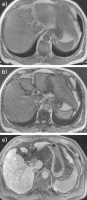

Abbildung 3a-c: MRT-Erscheinungsbild und MRT-KM-Anfärbeverhalten des steatotischen Adenoms. (a) In dem T1-gewichteten Bild In-Phase ist das kleine steatotische Adenom im Segment 7 (Pfeil) aufgrund des Fettgehalts hyperintens (= hell). (b) In dem T1-gewichteten Bild Opposed-Phase ist das kleine steatotische Adenom im Segment 7 (Pfeil) typischerweise hypointens (= dunkel) geworden, der Beweis für die Fetthältigkeit des Läsion. (c) 20 Minuten nach Gabe von Gadoxetat zeigt das kleine steatotische Adenom im Segment 7 (Pfeil) ein deutliches Auswaschen. Diese MRT-Merkmale erlauben die sichere Diagnose eines kleinen steatotischen Adenoms und indizieren eine Verlaufskontrolle.